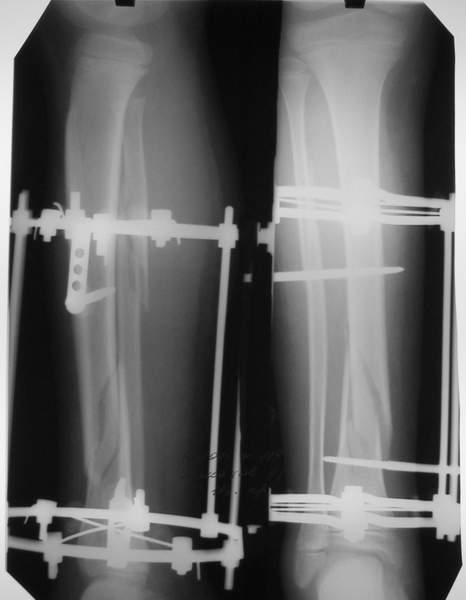

2

3a

3b

3c

В аттачте № 3 - один из примеров полукольцевого аппарат...

Это уже я баловался.

Итог? Работы больше (по времени и

интраоп "подгонке"), срастается также, а особого преимущества по сравнению с

"чиста" кольцевым (вес, удобство ношения и пр.) - я, по крайней мере,

не нашел.

Теперь не балуюсь.